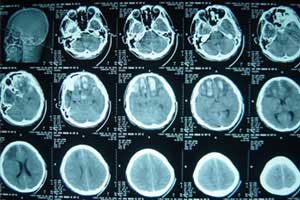

2.颅脑CT扫描 CT扫描采用观察软组织和骨质的两种窗位,将有利于颅骨平片所不能发现的骨折,尤其是颅底骨折。CT扫描可显示骨折缝隙的大小、走行方向,同时可显示与骨折有关的血肿,受累肿胀的肌肉。

粉碎性骨折进入脑内的骨片也可通过CT扫描三维定位而利于手术治疗。CT扫描还是目前惟一能显示出脑脊液漏出部位的方法。Bruce报道平扫定位率达50%,如采用碘剂脑池造影CT扫描则可达69%。

扫描时应注意不同部位采用不同方法。额窦 好应用轴位,筛窦、蝶窦及中耳鼓室盖部的骨折观察一般采用冠状扫描。应注意的是如果有损伤脊髓的情况存在,不易采用冠状扫描。